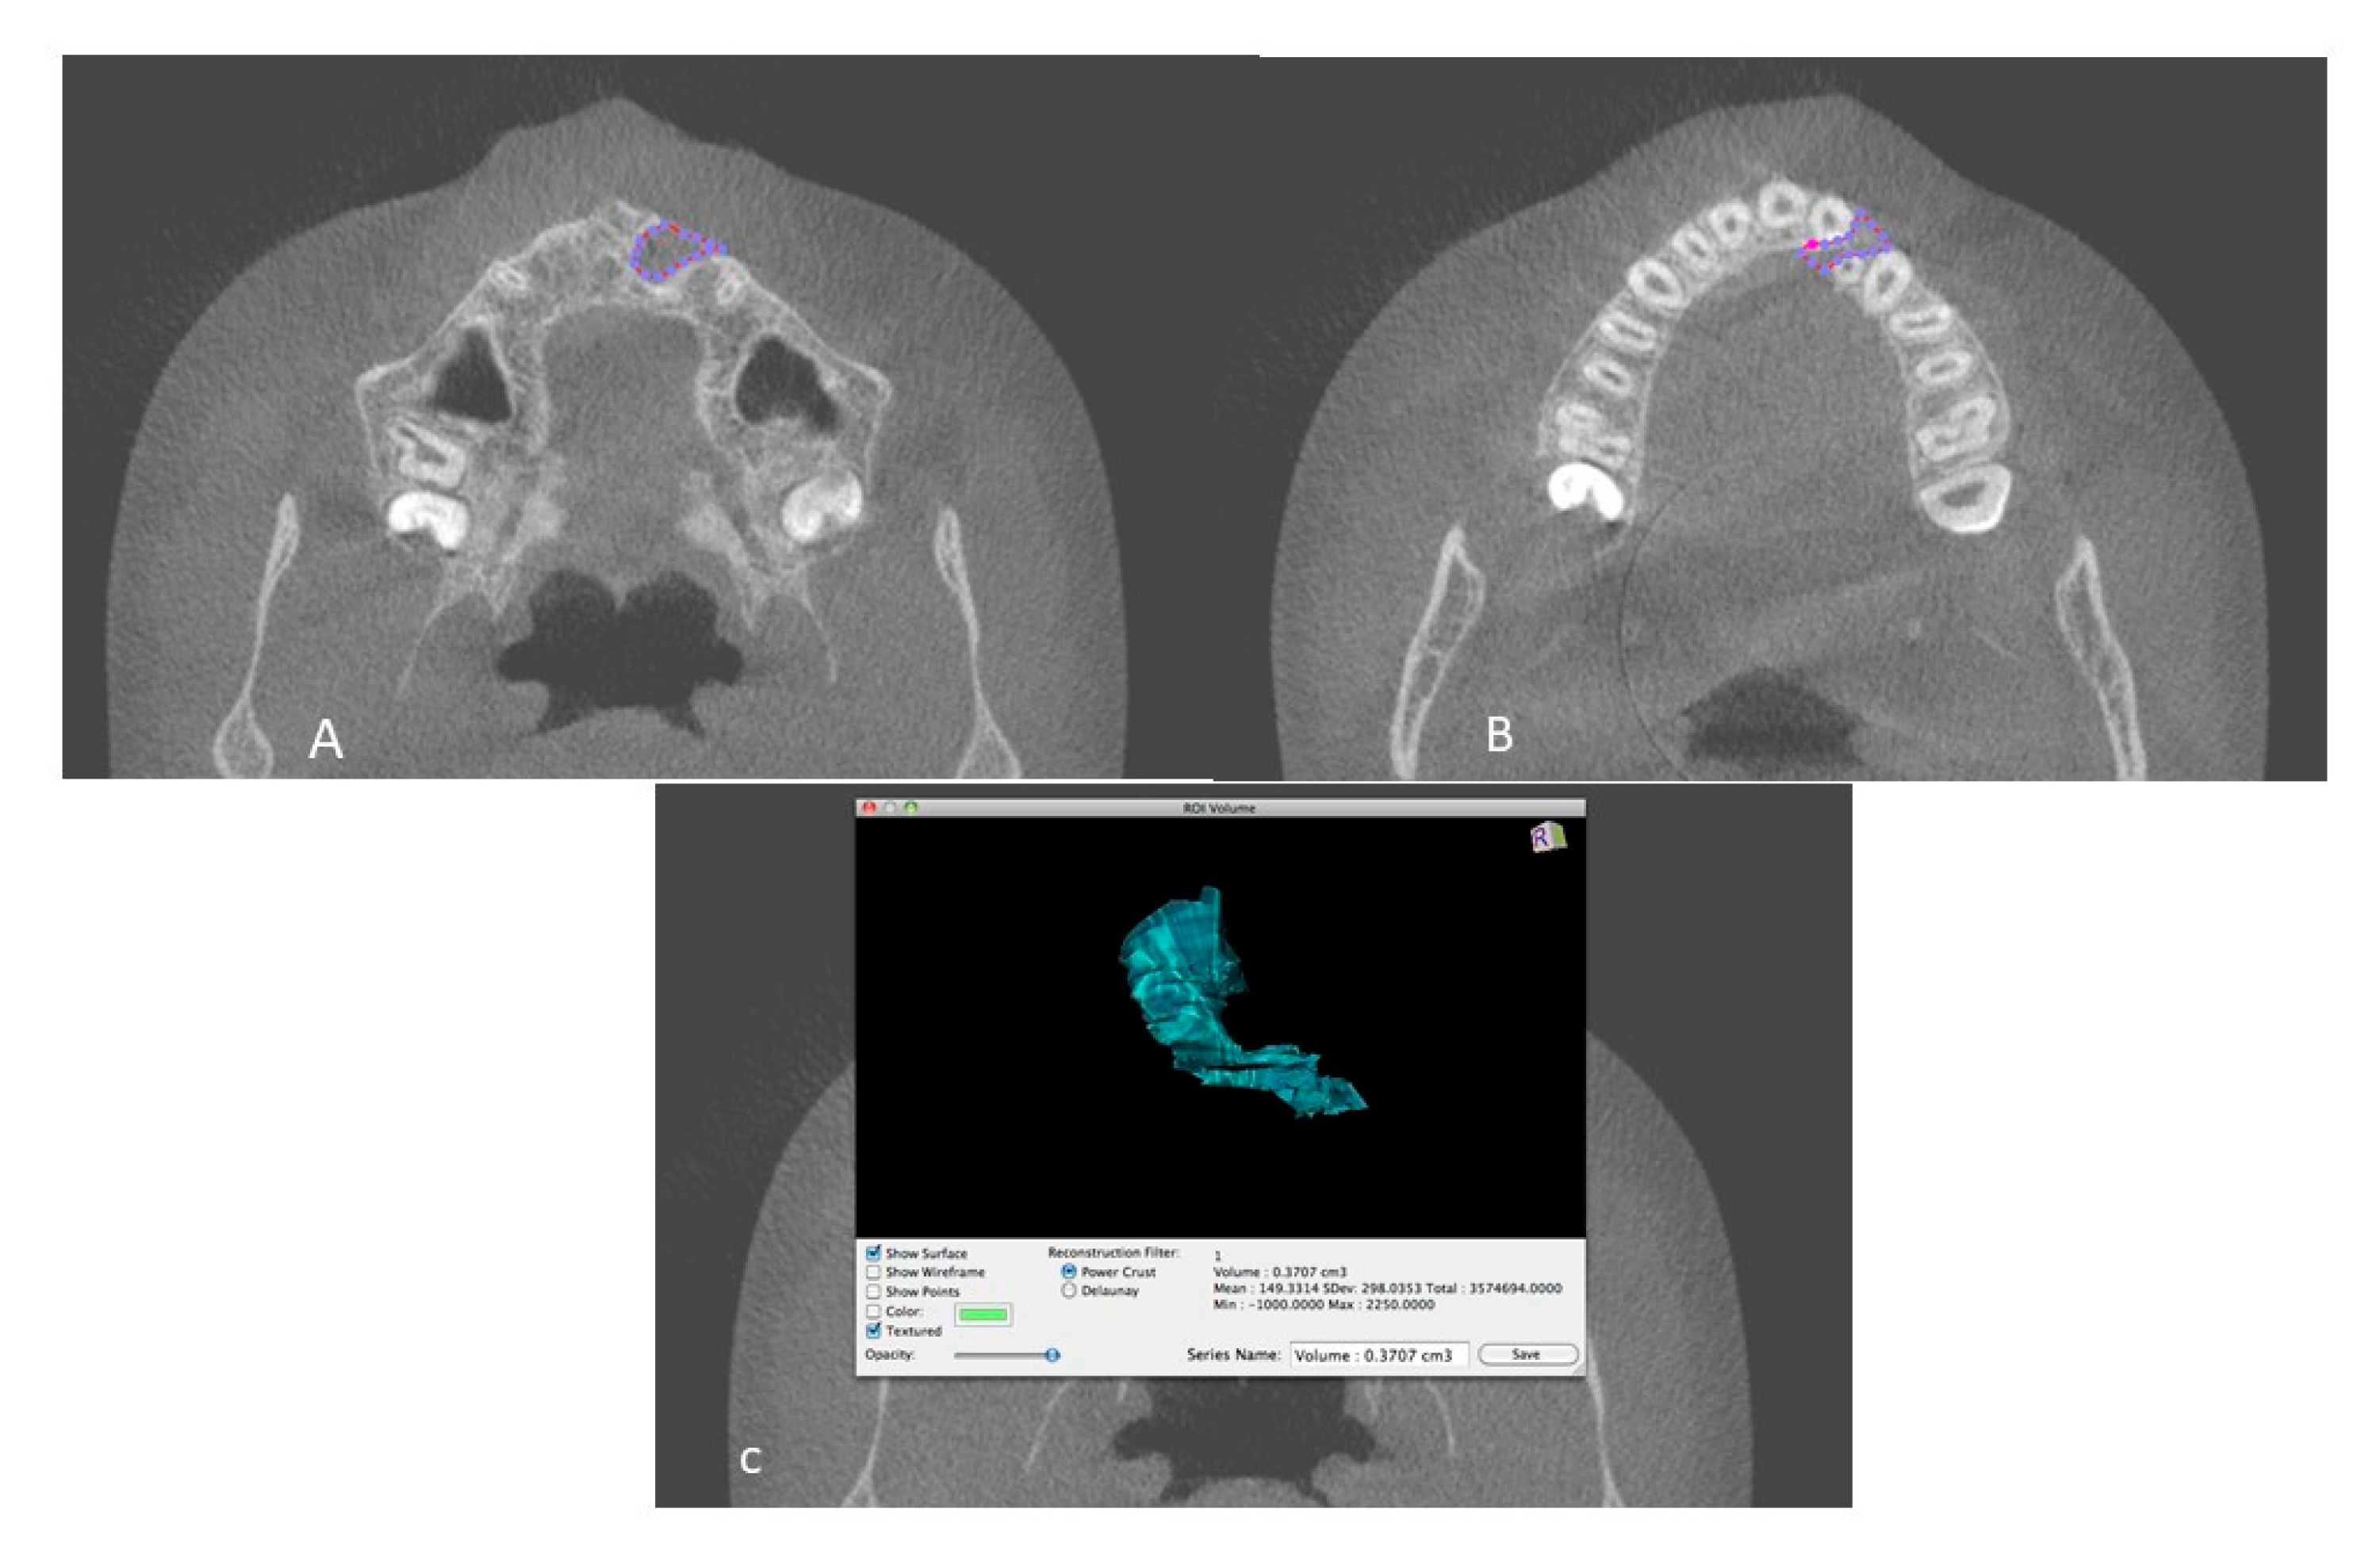

2.2. Measurements and Data Acquisition